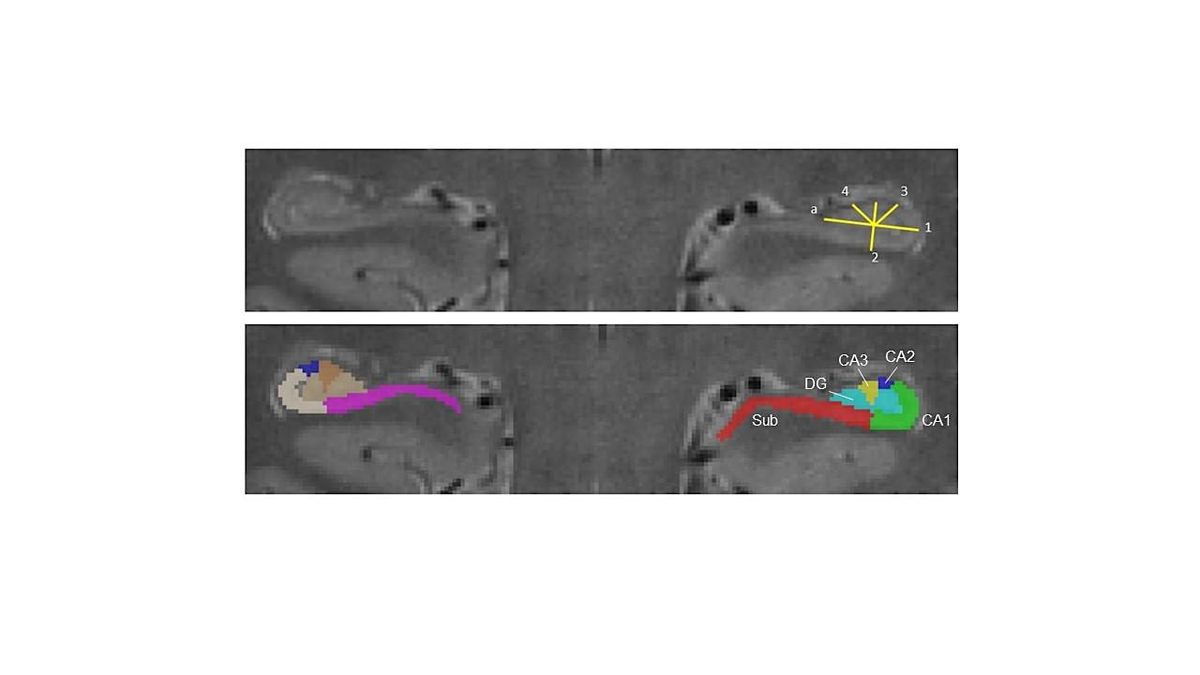

This workshop will provide an introduction to the Hippocampal Subfield Group (HSG) harmonized protocol for subfield segmentation in the hippocampal body, with hands-on training led by experts.

May 7, 2:30-5:00pm: An introduction to hippocampal and medial temporal lobe anatomy in the human brain, and an overview of the ITK-Snap software that we will use. Attendance is optional, and recommend for people at the novice level.

May 8, 9:30 am - 4:30 pm: Instruction and demonstration of the steps for the HSG harmonized protocol for subfield segmentation in the hippocampus body, including time to practice and gain direct feedback from experts in the room.